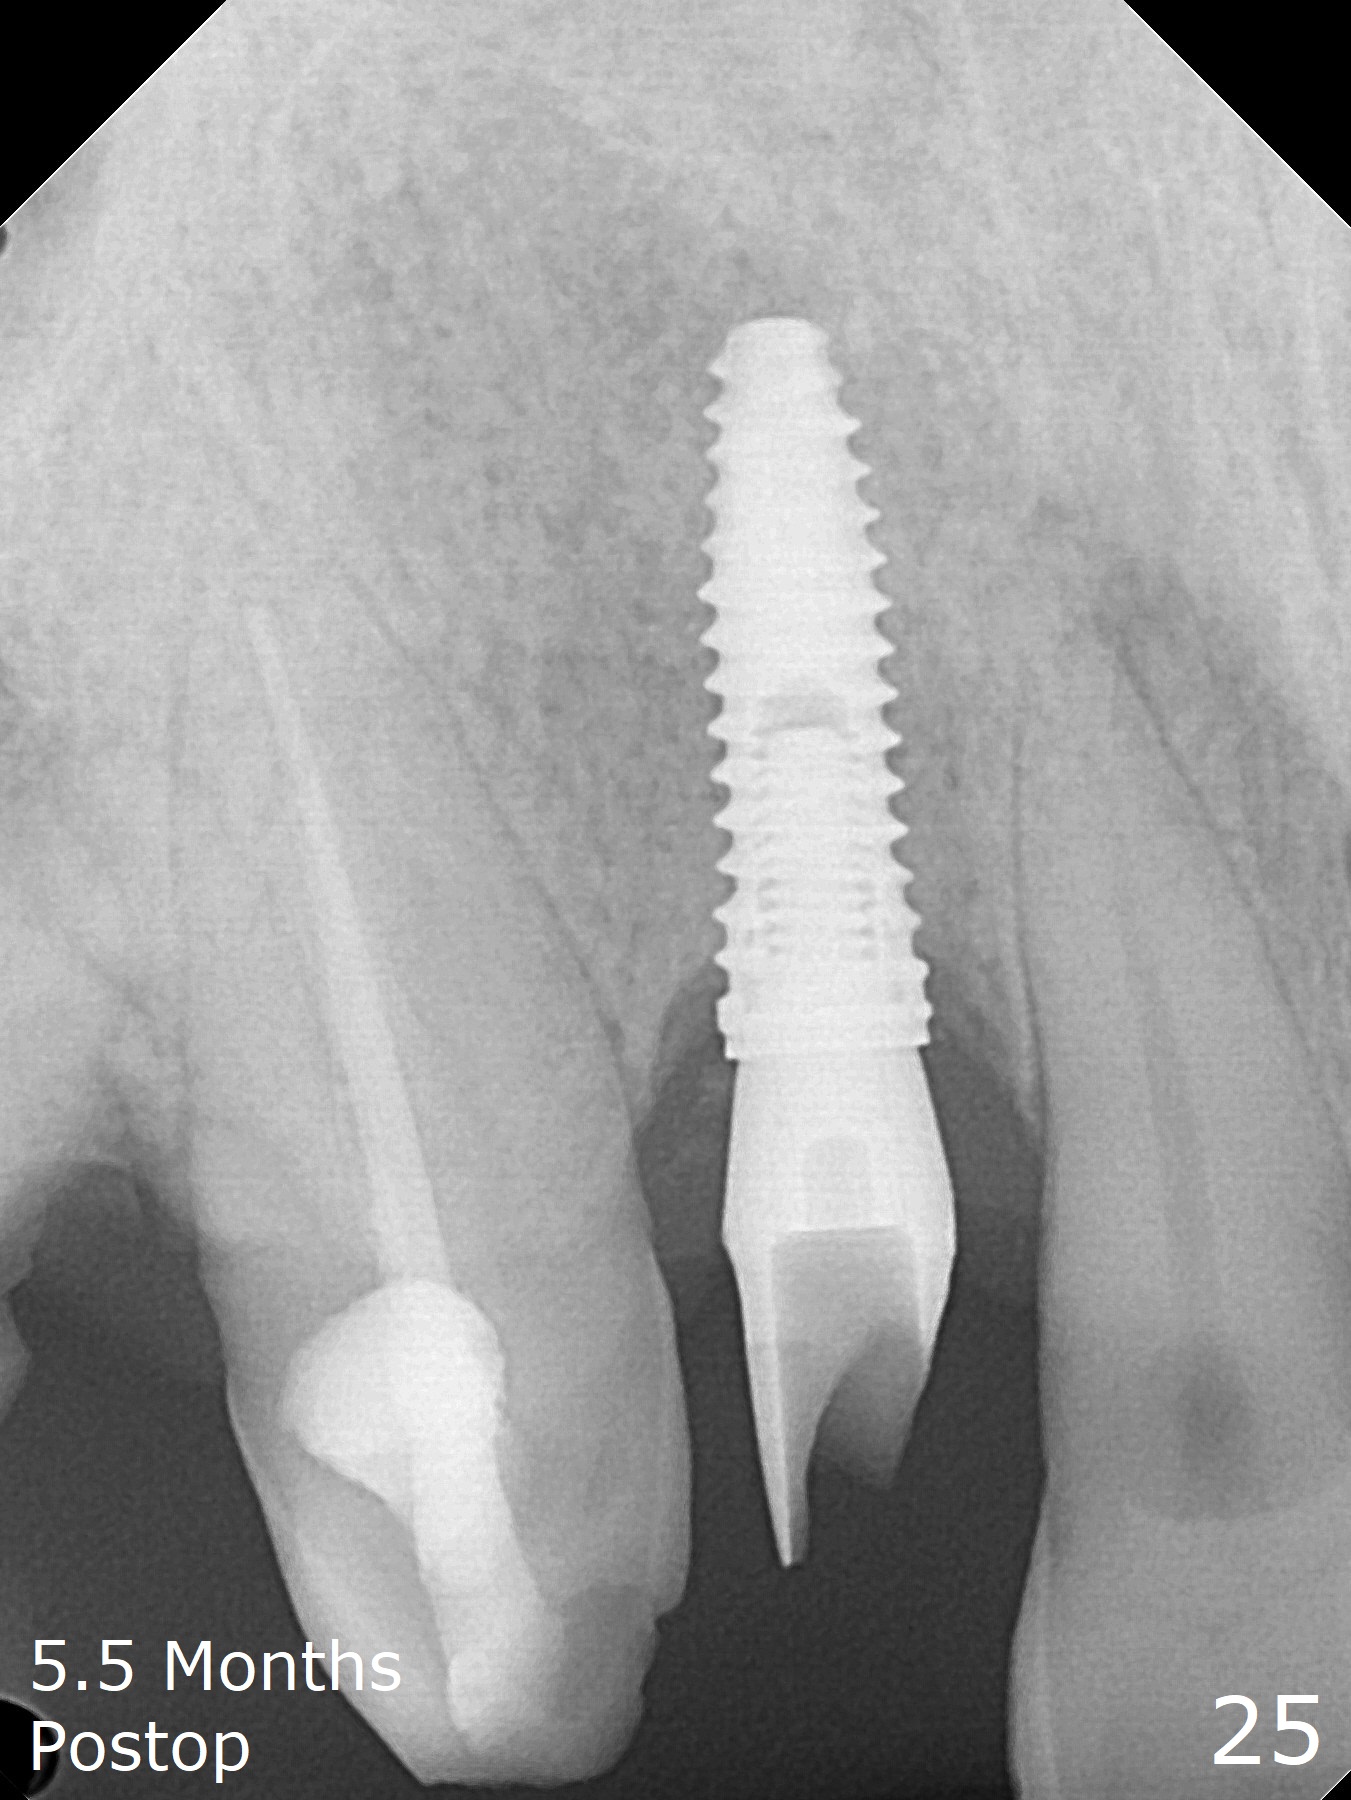

An apical abscess is present when the patient returns for immediate implant at #7 (Fig.1 *); a 2nd challenge is deep bite. After smooth extraction, the apical buccal plate is found to be perforated. Following debridement, a piece of gauze is placed in the apical defect for hemostasis, while osteotomy is initiated palatal (Fig.2). The apical defect seems to be extensive (Fig.3 yellow dashed line). A new trajectory is intended (red arrow) without much success. Before implant placement, bone graft is placed in the apical defect defect area, while a drill (Fig.4 D) is inserted in the finished osteotomy (Fig.5 O). In spite of seemingly large apical defect, the buccal crest bone exists (Fig.4 x). A 3x14(2) mm 1-piece implant is placed with stability; the first round of bone graft is apparently around the apical portion of the implant (Fig.6 *). The coronal end of the implant has to be adjusted several times buccopalatally to accommodate the deep bite. A 2nd round of bone graft following an immediate provisional closes the coronal space of the socket (Fig.7 *). CT will be taken to show the bone graft to repair the buccal plate defect when the patient returns for postop follow-up. In fact the defect is minimal in CT a month ago. The fistula does not disappear 1 week postop, but it is non tender (Fig.8). The patient complains of asymptomatic swelling in the right nostril. CT shows that the large buccal perforation is repaired with large amount of bone graft (Fig.9,10 *). It would be nicer to place the implant slightly more buccal apically (Fig.11 red lines; Fig.12 (preop design)). The buccoapical fistula disappears nearly 1 month postop (Fig.13). The apparently "lifeless" bone graft seems to be harmonious with the surrounding tissue (Fig.14). The periimplant gap reopens with implant mobility nearly 4 months postop (Fig.15), which is related to micro-movement associated with the immediate provisional. The latter is removed. A larger 2-piece implant will be placed in a 2-staged manner if needed (Fig.16). In fact the 3x14 mm straight 1-piece implant (Fig.17) has no mobility when it is retightened, but the trajectory remains buccal. Incision shows that there is no implant thread exposure. A 3x14 mm 15 degree angled 1-piece dummy implant is able to establish the correct trajectory, but there is no occlusal clearance (Fig.18). Micromovement during osteointegration may recreate loosening. Finally using Lindamann bur, the osteotomy is changed so that a 3.5x13 mm 2-piece implant does not need an angled abutment to establish occlusion (Fig.19). There is one palatal thread exposure. Allograft is placed circumferentially, followed by Human Amnion-Chorion Allograft and Collagen Plug. The wound does not heal 8 days postop (Fig.20), as related to the age (79 years old)? The wound appears to heal with a membrane on the surface (Amnion-Chorion one?) 3 weeks postop (Fig.21). The ridge looks wide 3.5 months postop (Fig.22,23). A 4.5x5.5(3) mm appears to be seated incompletely with a gap between the abutment and the implant (Fig.24<). A provisional is fabricated after heavy palatal reduction. Two months later, the provisional fractures. After repositioning the abutment with complete seating and torque (Fig.25), impression is taken. Although the buccal plate is concave, the gingiva remains healthy 10 months post cementation (Fig.26,27).